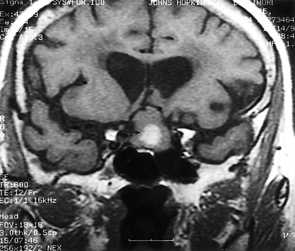

МРТ головного мозга. Т1-взвешенная корональная МРТ. Смешанный ишемический инсульт. Ранняя подострая стадия.